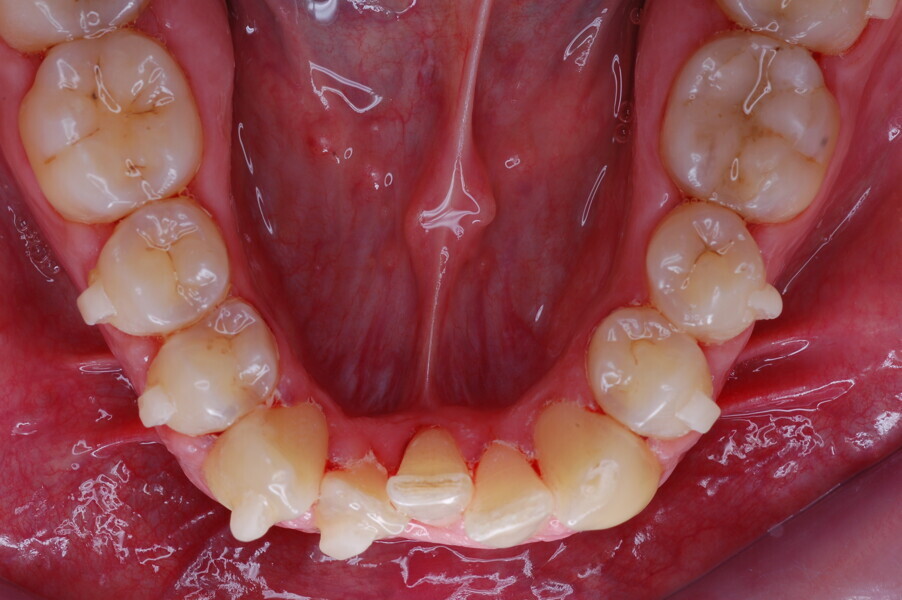

Figs. 1–8: Pretreatment facial and intra-oral photographs.

From the periodontal point of view, the patient showed a good attitude to oral hygiene, but crowding of the mandibular incisors made cleaning difficult in that area, causing plaque accumulation and localised gingival inflammation. The panoramic radiograph revealed the presence of the mandibular third molars and confirmed the absence of the mandibular right central incisor (Fig. 10).

The cephalometric analysis showed a skeletal Class II malocclusion (convexity of Point A: 4.9 mm), a slightly retruded chin position (facial depth: 78.1°) and a skeletal open bite tendency (lower facial height: 53.19°; facial axis: 80.58°; Fig. 9). The mandibular incisors were lingually tipped (Li–APog: 9.3°) and retruded (Li–APog: 1.55 mm), and there was an increased inter-incisal angle of 142.9°.